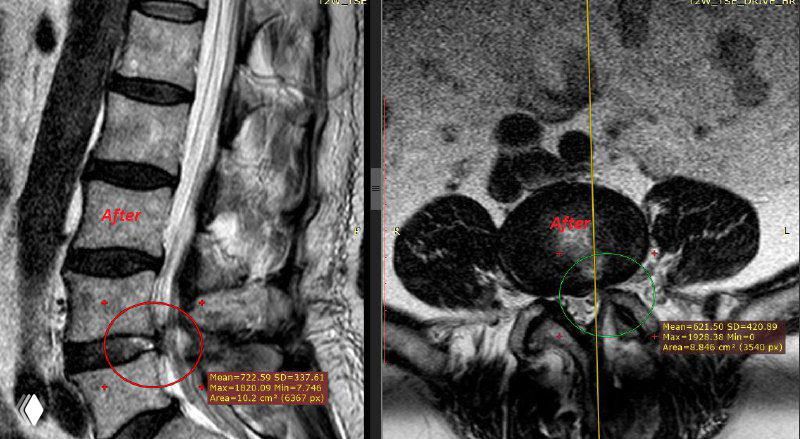

После корректно выбранной тактики и третьего вмешательства болевой синдром полностью купировался.

Особенность случая — парамедианно-фораминальное, с элементами экстрафораминального, расположение грыжи.

Такие варианты технически сложны и требуют адекватного доступа.